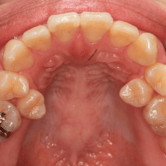

Dientes supernumerarios

Los dientes supernumerarios son dientes adicionales que pueden aparecer en la boca de un niño, generalmente en la región anterior del maxilar.

Los padres pueden notar dientes adicionales en la boca de sus hijos, lo que puede causar apiñamiento o problemas de alineación.

El tratamiento incluye la evaluación y, en algunos casos, la extracción de los dientes adicionales para permitir un desarrollo dental normal